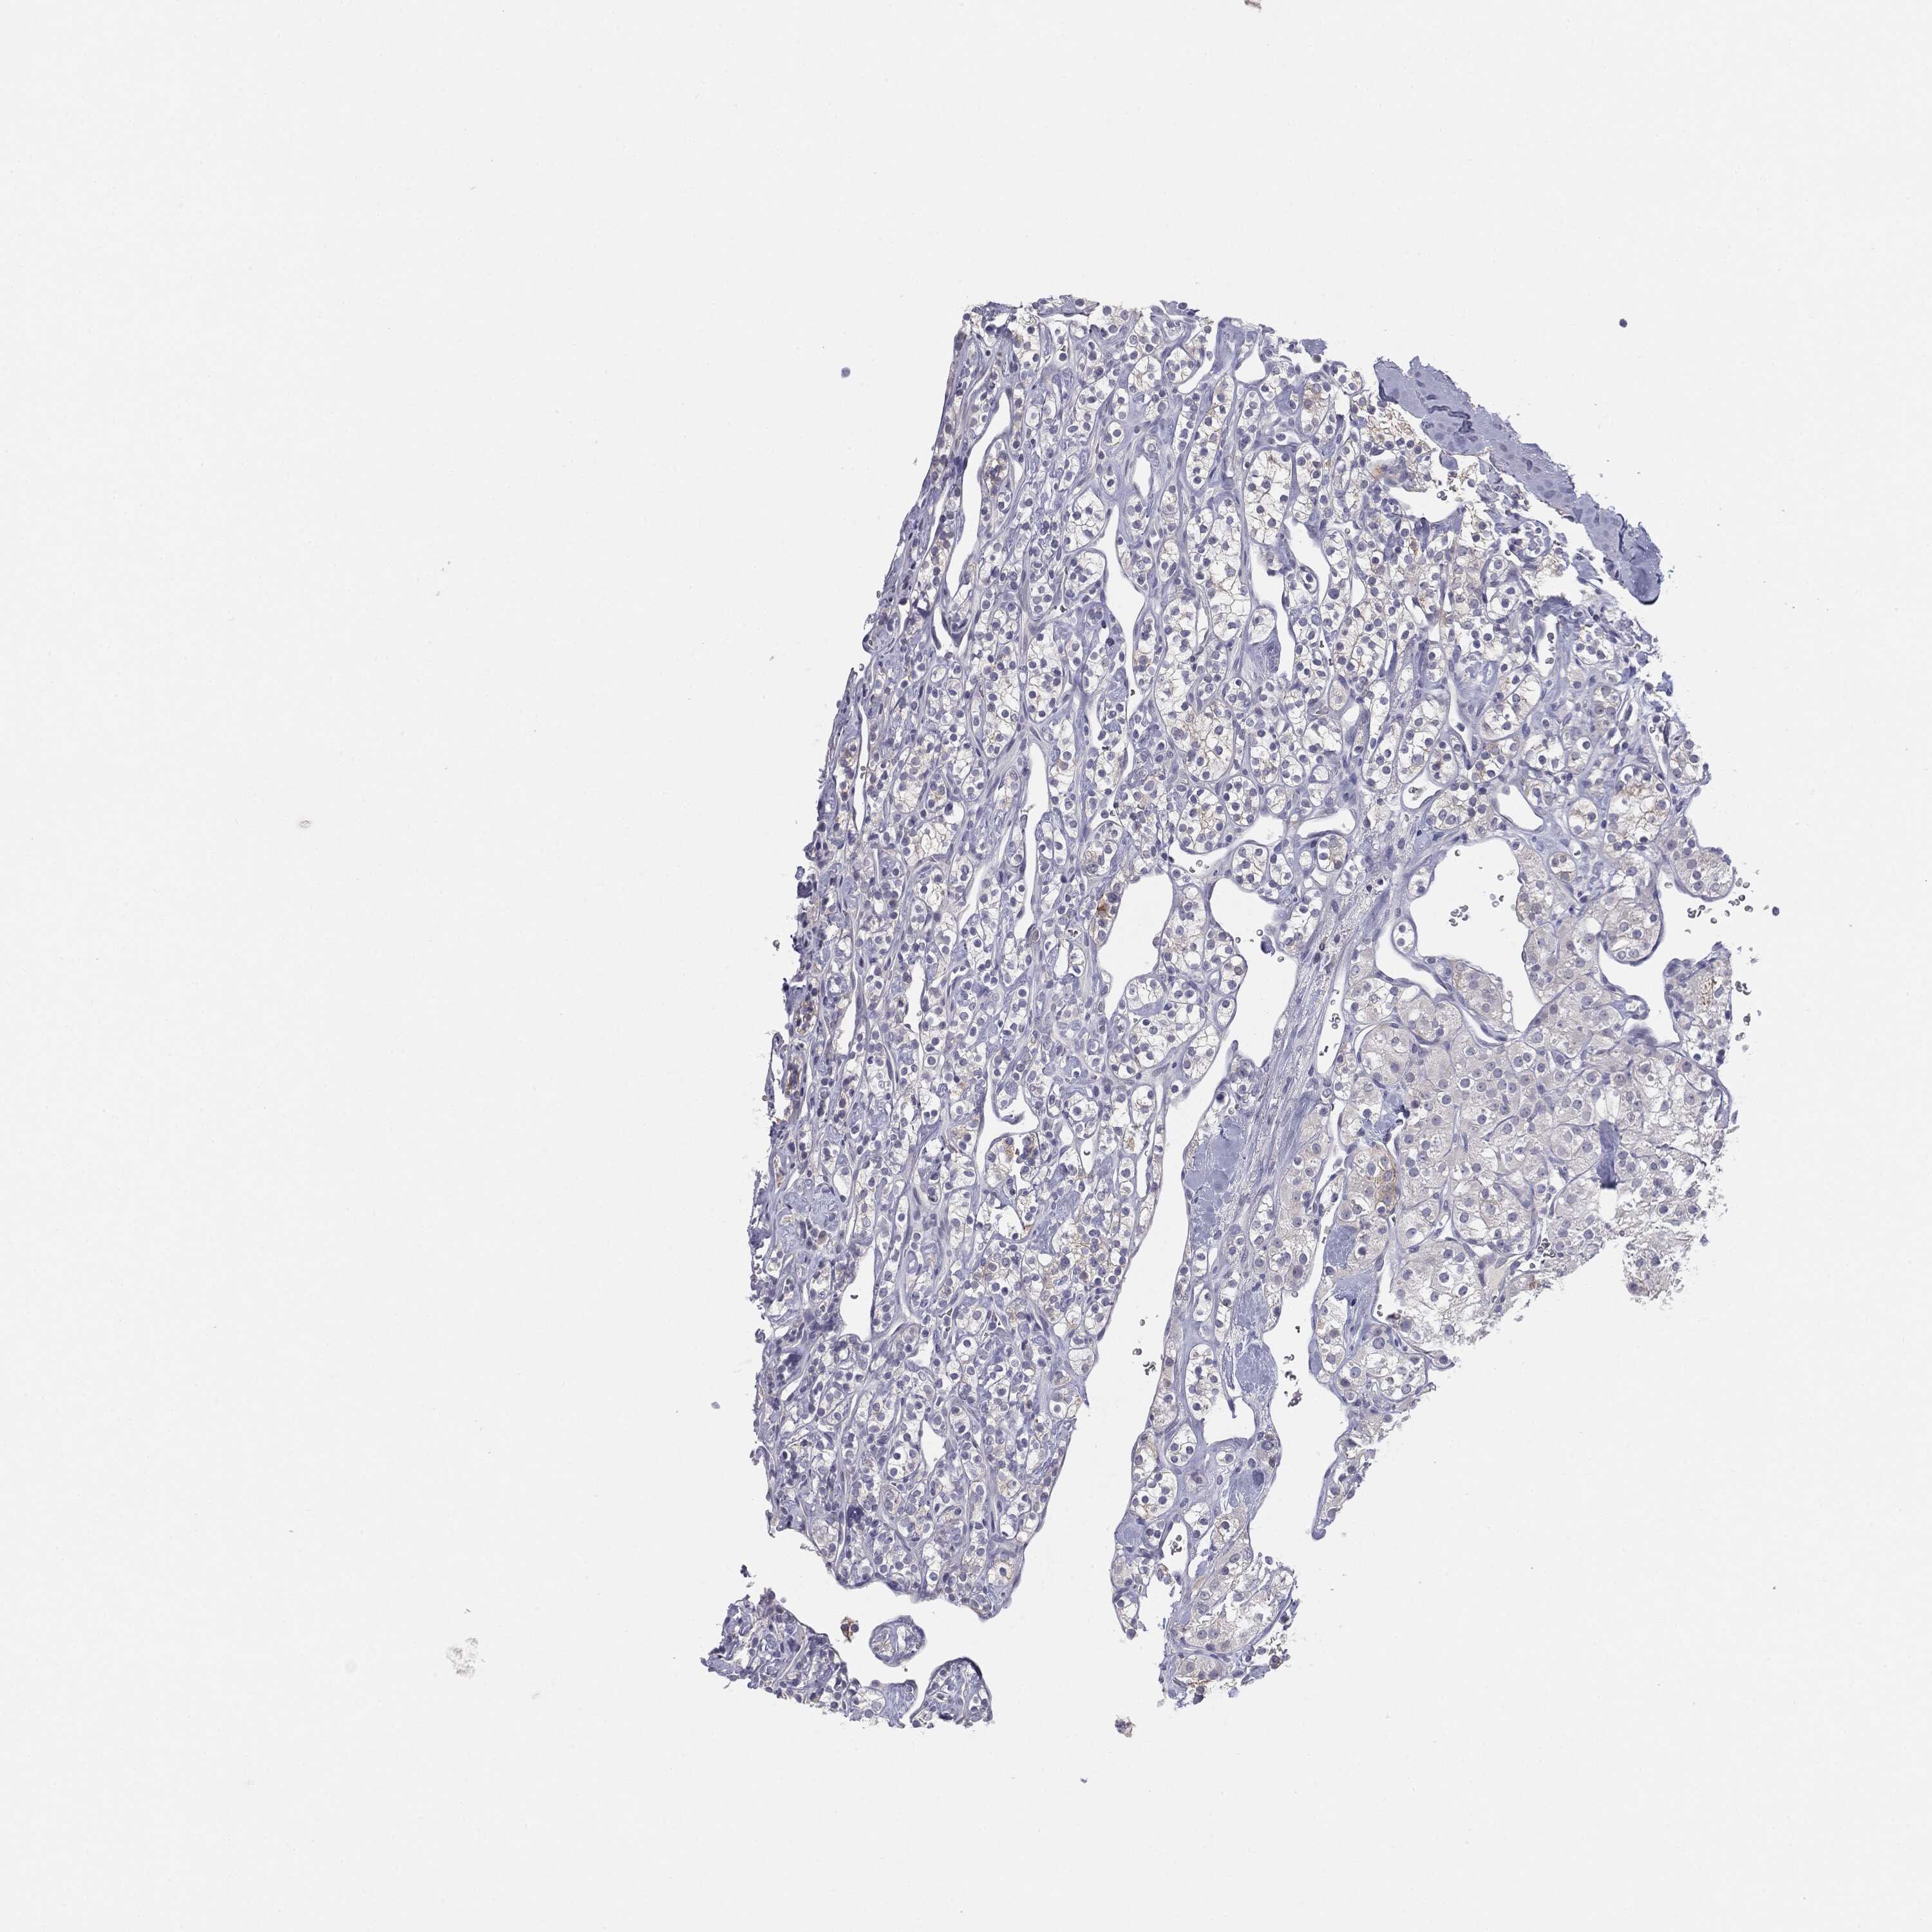

MUC1 is not prognostic in Kidney Renal Papillary Cell Carcinoma (TCGA)

Current cut offi

Current cut-off shows the cut-off (FPKM) currently selected. It may be changed manually. When the current cut-off is changed, the vertical dashed line indicating cut-off, the interactive survival scatter plot and the Kaplan-Meier curve will be automatically adjusted to show results accordingly.

:

Best expression cut offi